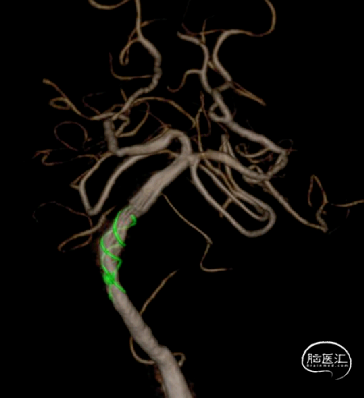

3D旋转造影

通过3D工作位测量出基底动脉瘤瘤颈最宽处:6.5mm;载瘤动脉尺寸:近端直径3.7mm,远端直径4.2mm。

3D重建